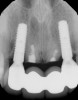

The patient, a healthy 45-year-old nonsmoking woman (American Society of Anesthesiologists [ASA] II), presented with a failed maxillary central incisor due to severe internal-external root resorption (Figure 1). She had a high esthetic risk profile based on 12 presenting esthetic risk factors (key No. 1), including a high lip line, high esthetic expectations, and adjacent teeth that had been restored (Figure 2).Site-specific CBCT (Carestream CS 9300, Carestream Dental, carestream.com) noted a thick intact buccal plate and a class 1 sagittal root position (Figure 3 and Figure 4). Preplanning with a bone-level 4.1-mm diameter x 14-mm long implant (Straumann Bone Level Roxolid® SLActive, Straumann, straumann.com) assured a 3-mm buccal gap upon placement and a screw-retained position (key No. 2). Prior to placement, intact buccal and palatal walls were confirmed. Figure 5 shows palatal wall placement of the implant after minimally traumatic flapless tooth extraction. An anatomically correct surgical guide template was used to assure a screw-retained position and correct vertical depth of approximately 4 mm from the mid-buccal apical extent of the guide template, which correlated to 1 mm apical of the intact buccal plate (key Nos. 3 through 5). The two-unit (8-9x cantilever) fixed provisional was recemented post-surgery. The 3-mm buccal gap was grafted tightly with a low-substitution DBBM (Bio-Oss®, Geistlich Pharma, geistlich-na.com) (key No. 6), and a pouch was created with a Buser membrane instrument (Hu-Friedy, hu-friedy.com) from line angle to line angle as a mini full-thickness flap to the mucogingival border to accept a connective tissue graft (Figure 6). The connective tissue graft, 1-mm thick x 12-mm long x 7-mm wide (Figure 7), was harvested from the palate (key No. 7).

Fig 3. Pretreatment site-specific CBCT showing thick intact buccal plate and class 1 sagittal root position. Preplanning with a bone-level 4.1-mm diameter implant assured a 3-mm buccal gap upon placement and a screw-retained position.

Figure 3

Fig 4. Pretreatment site-specific CBCT showing thick intact buccal plate and class 1 sagittal root position. Preplanning with a bone-level 4.1-mm diameter implant assured a 3-mm buccal gap upon placement and a screw-retained position.

Figure 4